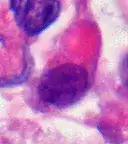

AT/RT and rhabdoid tumor share the term "rhabdoid" because under a microscope, both tumors resemble rhabdomyosarcoma.

Rhabdoid Tumor Cell - 400X Magnification

Histology

The tumor histopathology is jumbled small and large cells. The tissue of this tumor contains many different types of cells including the rhabdoid cells, large spindled cells, epithelial and mesenchymal cells, and areas resembling primitive neuroectodermal tumor (PNET). As much as 70% of the tumor may be made up of PNET-like cells. Ultrastructure characteristic whorls of intermediate filaments are seen in the rhabdoid tumors (as with rhabdoid tumors in any area of the body). Ho and associates found sickle-shaped embracing cells, previously unreported, in all of 11 cases of AT/RT.[24]